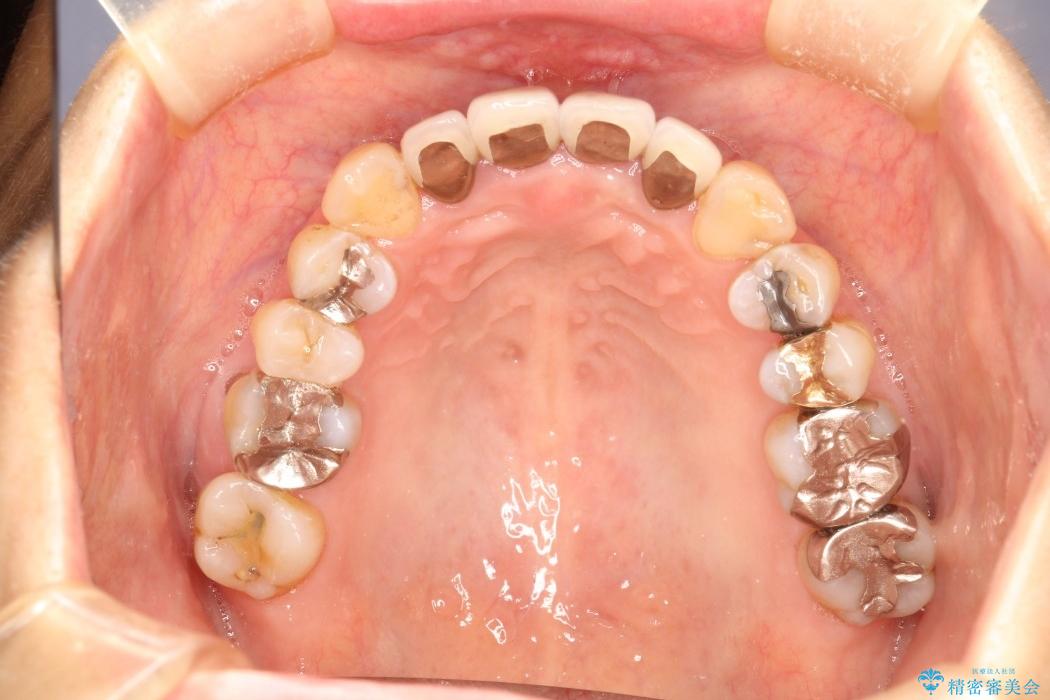

【50代女性】八重歯のインビザライン矯正 治療例

八重歯の改善を希望され来院されました。

当初はセラミックでの治療を希望されていましたが、噛み合わせと歯並びを治していく為に矯正治療を提案させていただき、インビザラインでの矯正を行う計画にしました。

頻繁にご来院いただく事が難しかったこともあり、型取りのし直し(リファインメント)を2回行いました。時間はかかってしまいましたが、患者様には大変ご満足していただくことができました。